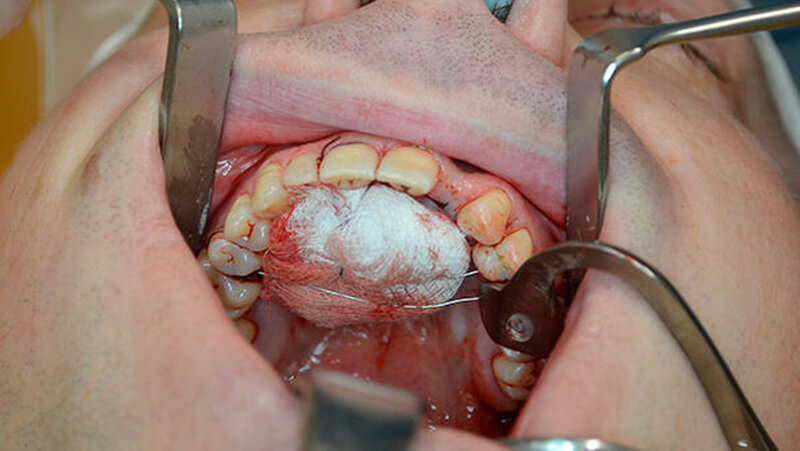

Zur weiteren Abklärung erfolgte eine dreidimensionale Bildgebung mittels DVT (Abbildung 3). Hier zeigte sich eine gut abgrenzbare Raumforderung im Bereich der Oberkieferfront mit Kontakt zum Canalis incisivus. Es wurde eine Zystektomie mit palatinaler Aufklappung in Kombination mit einer Beckenkammaugmentation durchgeführt. Intraoperativ kam es nach Injektion der Lokalanästhesie zu einem Spontanprolaps eines Idoformstreifens palatinal (Abbbildung 4).

Die Zyste wurde in toto exstipiert und zur weiteren Diagnostik in die Pathologie abgegeben (Abbildung 5). Auf Grund eines Zystenvolumens von mehr als 2cm3in der DVT-Diagnostik wurde eine Knochenaugmentation mittels Beckenkammspongiosa durchgeführt. Nach enoralem Wundverschluss wurde ein Überknüpfverband mittels Iodoformvaselinestreifen angelegt und mittels Drahligaturen interdental fixiert (Abbildung 6).